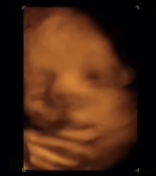

El nuevo libro del embarazo y el nacimiento: una guía práctica y completa para futuros padres Miriam Stoppard. Editorial Grijalbo En este manual encontrarás la información y orientación sobre cada etapa, desde la planificación previa hasta los primeros días del recién nacido. Muestra un...